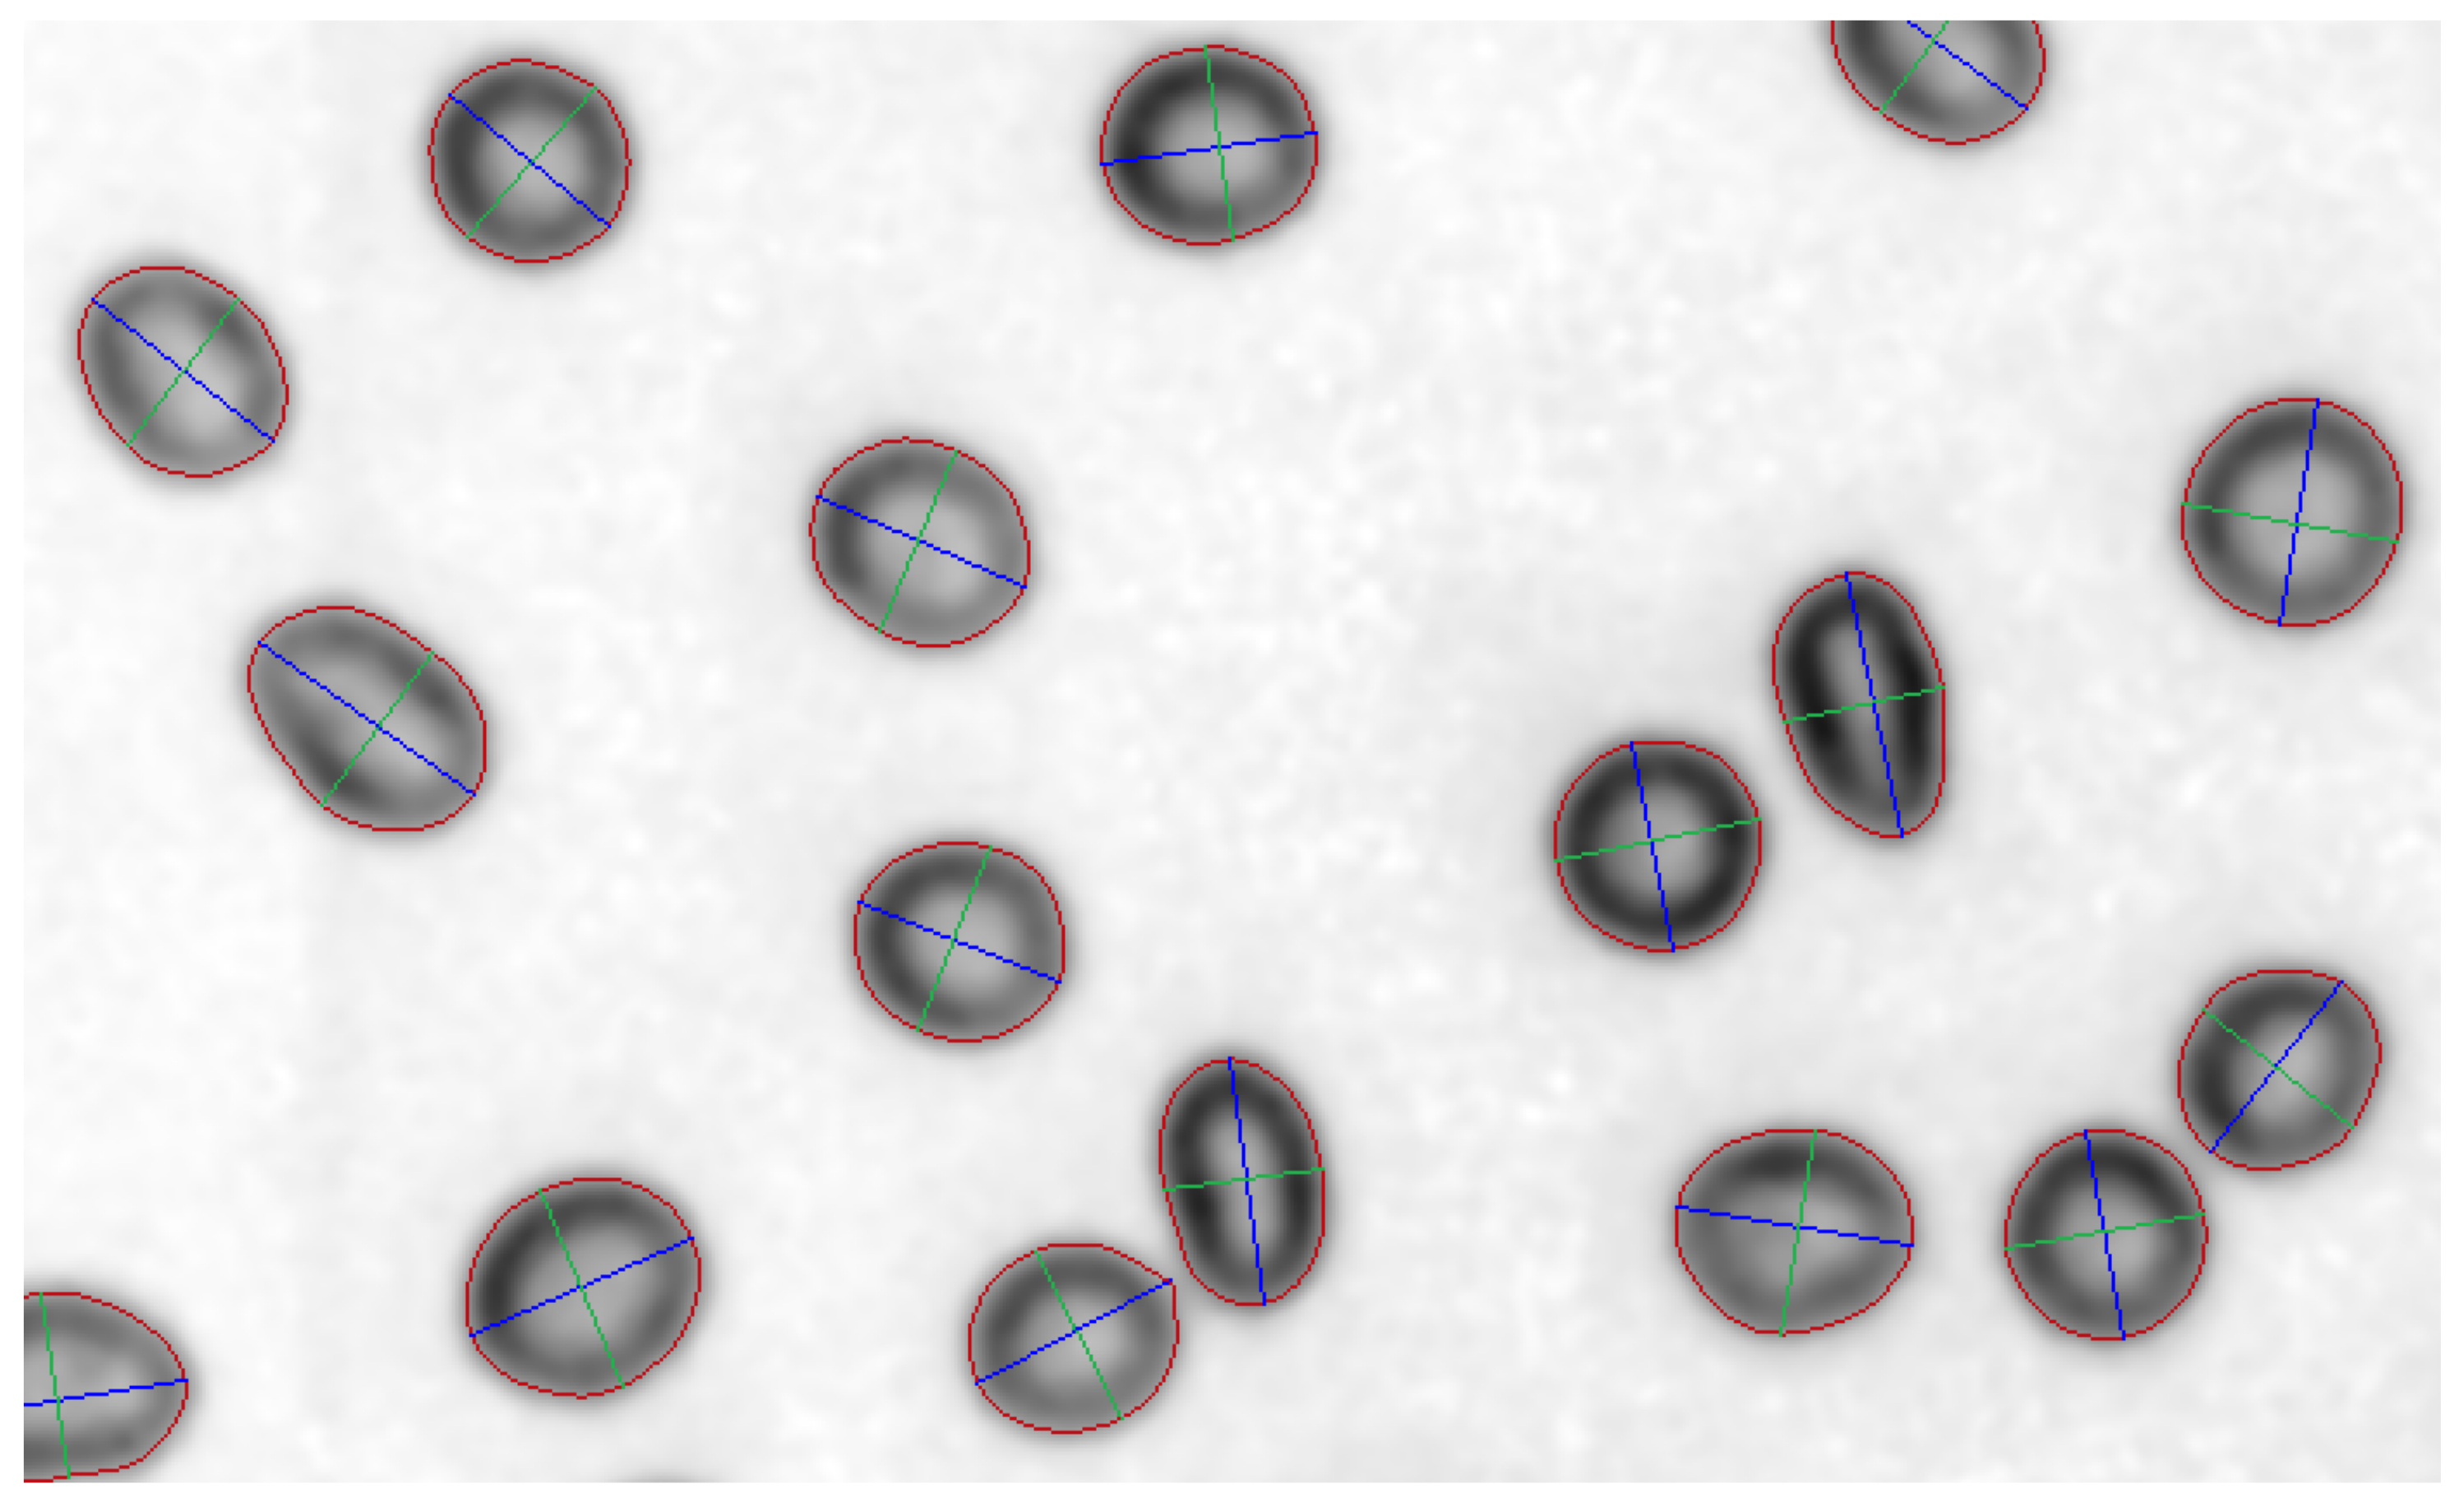

3.2. Individual Object Processing and Segmentation

4. Results